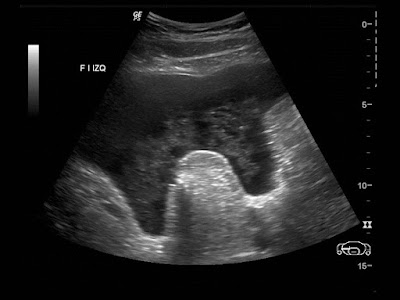

Paciente de 12 años con dolor abdominal. Remitida para estudio de masa intraabdominal.